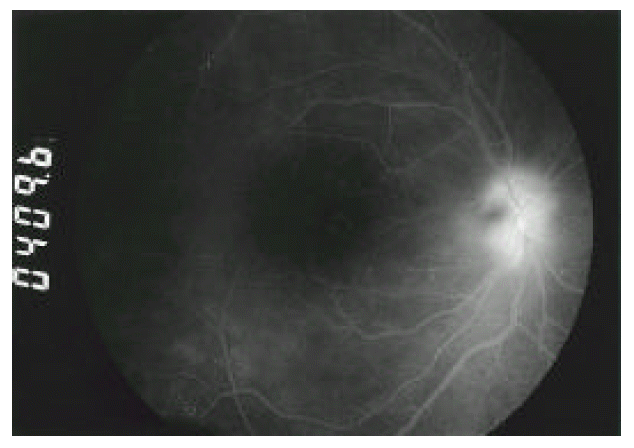

Initially he was treated with indomethacin 50 mg/day, sulfasalazine 2g/day, methotrexate 7.5 mg/week and colchicine 1.2 mg/day. Because of persisting, painful swelling of the right knee, methotrexate was increased to 15 mg/week, and intra-articular injection of triamcinolone acetonide 40 mg was done. While being treated, recurrent acute iritis with hypopyon, posterior uveitis and papillitis in both eyes (Figure 3 & 4) were developed. Prednisolone 40 mg/day and cyclosporine 5 mg/kg/day were prescribed.

Fig. 4.

Fluorescein angiogram of the right eye reveals prominent leaking of optic disc and diffuse hyper-fluorescence due to posterior vitritis.